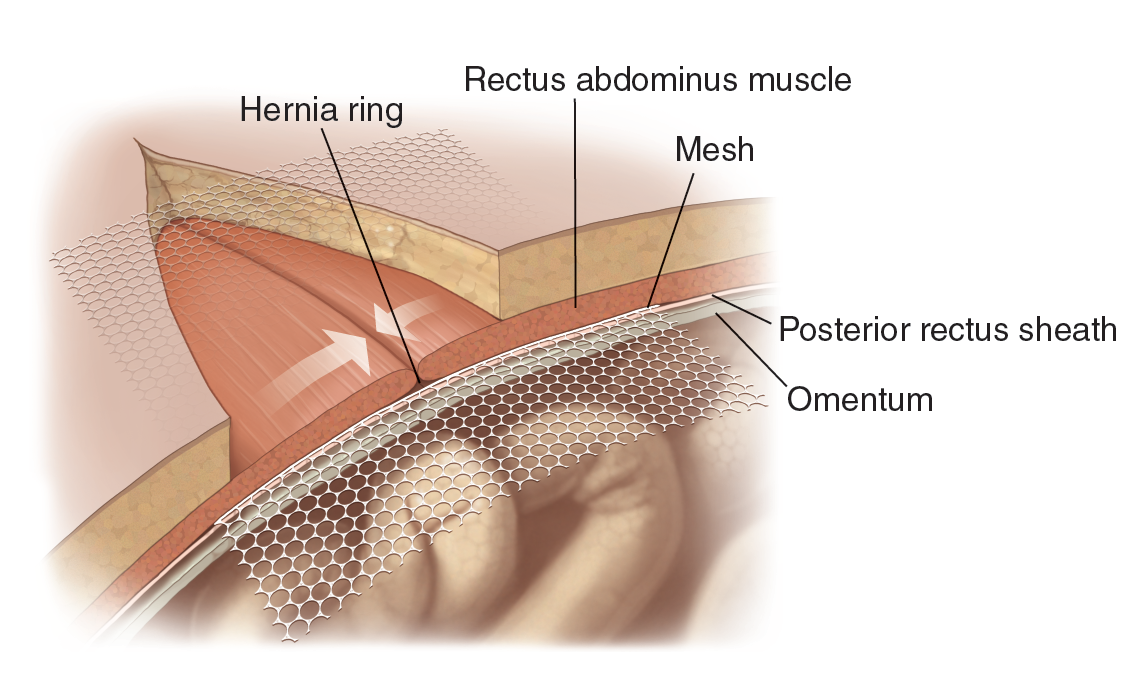

Medical Illustration

All images are works made for hire and are the exclusive property of the client. These are shown as sample purposes of my work only. For licensable work, please see my Illustration Services page.

Medical Illustrator for Precision Graphics, Lachina, and Human Kinetics Publishing (current)

Contract freelancer for many others, some examples of my work below.